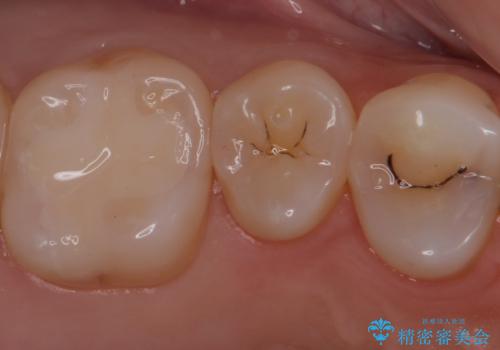

銀歯をセラミックにやり替えることで審美性を改善することができます。

適合の良いセラミックインレーを装着することで、今後の虫歯発生リスクを抑えることができます。